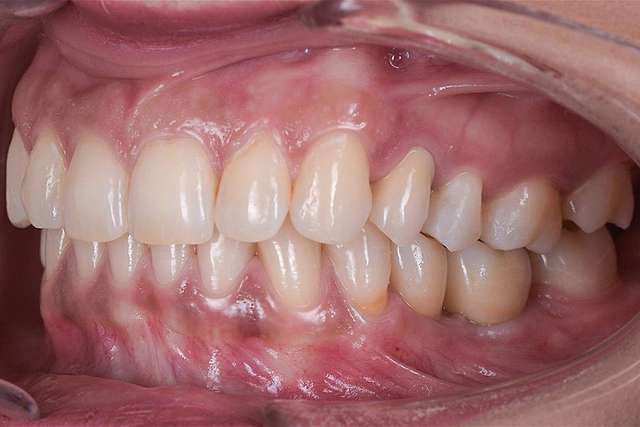

Reduced Trauma

When implant therapy is performed with guided surgery, the surgery itself is simpler, and trauma is reduced especially for the soft-tissues. Overall we can achieve faster healing and better post-op comfort.